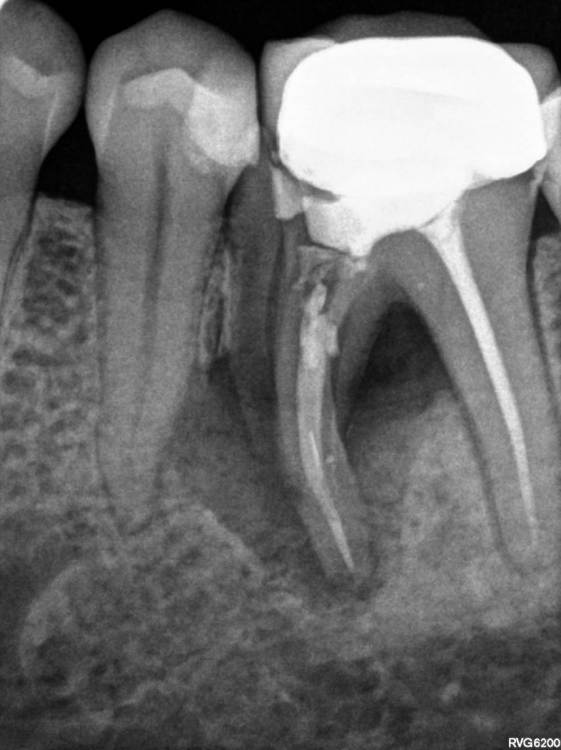

TIGER Опубликовано 14 июля, 2023 Автор Поделиться Опубликовано 14 июля, 2023 всем привет!Не всегда одномоментная имплантация метод выбора,в данном кейсе пошёл по более прогнозируемому пути для сохранения тканей 1 1 Ссылка на комментарий

TIGER Опубликовано 14 июля, 2023 Автор Поделиться Опубликовано 14 июля, 2023 @Fin 2 й этап имплант&нкр Ссылка на комментарий

Irouil Опубликовано 15 июля, 2023 Поделиться Опубликовано 15 июля, 2023 Интересно, одномоментно в лунку дистального корня не зашло бы? Предположу, что либо ангуляция вышла бы экстремальной, либо слишком близко к вестибулярной стенке пришлось бы ставить Вообще, эти случаи с выраженным поднутрением в боковых отделах нижней челюсти достаточно коварные, на мой взгляд, с точки зрения позиционирования 1 Ссылка на комментарий

TIGER Опубликовано 15 июля, 2023 Автор Поделиться Опубликовано 15 июля, 2023 @Irouil было бы сложно стабилизировать в этих условиях,в случае неуда ситуация усугблялась,решил пойти по пути сохранения тканей,дал организму самому регенирировать,при имплантации добавил чуть тканей @Doc ещё Миш писал в книге о минусах имплантации семёрок кстати 1 Ссылка на комментарий